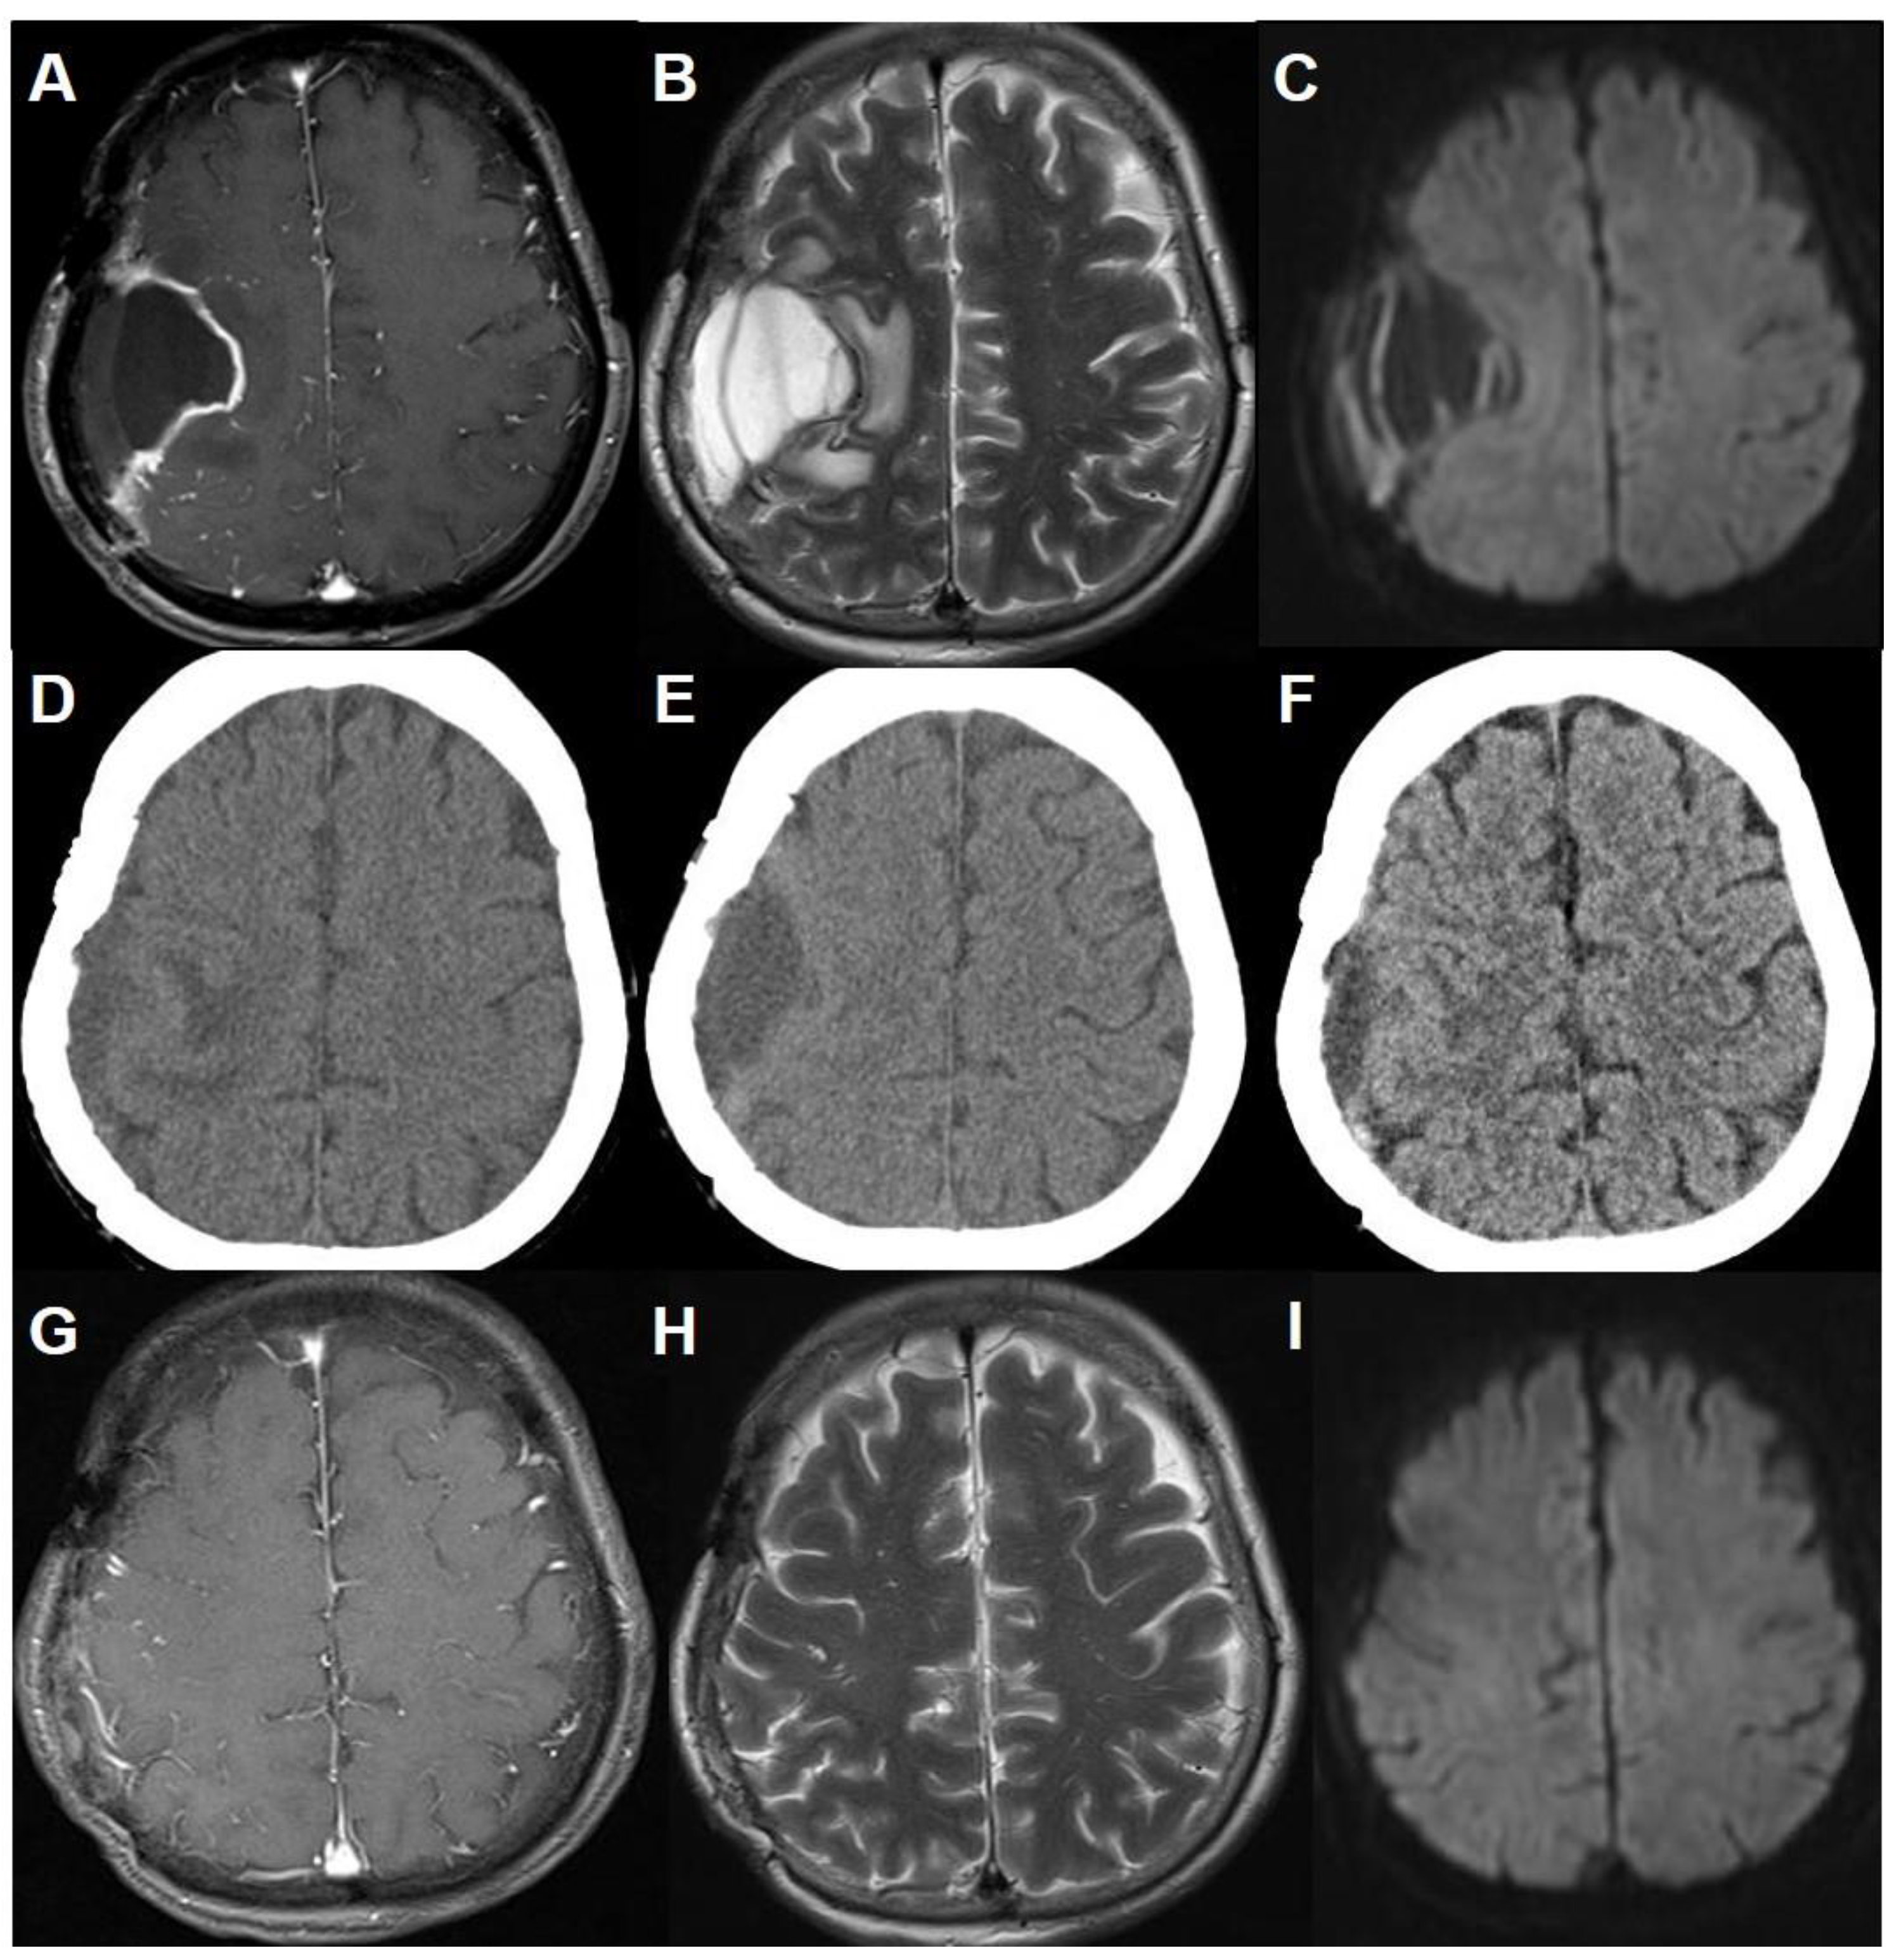

A 58-year-old right-handed female presented to the clinic with a headache of long duration and a two-week history of posterior neck pain. She had no significant medical or family history. No other neurological deficits were noted. Brain computed tomography (CT) scans and magnetic resonance (MR) images demonstrated a homogeneously enhanced, calcified, and multi-lobulated mass adjacent to the right motor strip without peritumoral edema (Figure 1A–C). The patient underwent a craniotomy for tumor resection without incident or residual deficit. The arachnoid plane between the multi-lobulated tumor and the motor strip was well-preserved. The surrounding vascular structures were also not injured during surgery except for venous bleeding from the mass stump, which was controlled by a fibrin sealant patch and oxidized cellulose (Figure 1D). A dura mater defect was repaired with an artificial dura substitute. There were no abnormal changes on intraoperative monitoring for motor-evoked potential and somatosensory-evoked potential during surgery. The postoperative CT scans showed the usual postoperative changes without hemorrhage or infarction (Figure 1E). Histopathologically, the mass was confirmed as fibrous meningioma. The patient recovered well uneventfully.

Figure 1. Perioperative images. (A) Brain CT scan, and (B) gadolinium-enhanced T1-weighted and (C) T2-weighted axial MR images showing a homogeneous enhanced, calcified, and multi-lobulated mass adjacent to the right motor strip without perilesional edema. (D) Intraoperative photograph demonstrating gross total resection without definitive cortical injury. Small arachnoid disruption and venous bleeding was controlled by a fibrin sealant patch and oxidized cellulose at the mass stump. (E) Brain CT scan immediately after resection showing air-bubbles in the resection bed, which were due to hemostatic agents. This is indicated by an asterisk in the operative photograph.